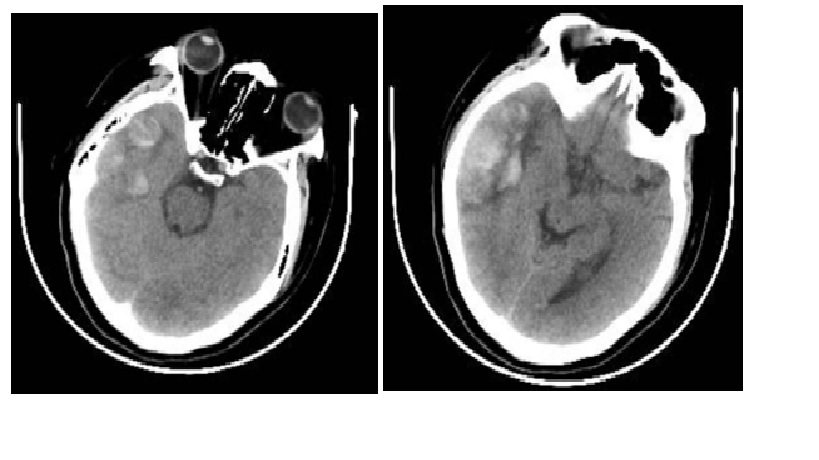

CT đầu nên được thực hiện trong cấp cứu để loại trừ xuất huyết và thoát vị não. Tìm:

• Dấu hiệu delta trống (Empty delta sign) – dòng chảy trống trong xoang dọc sau do huyết khối xoang dọc trên.

• Dấu hiệu xoắn ốc (Corkscrew sign) – các nhánh tĩnh mạch giống hình dạng “xoắn ốc” sau khi hình thành huyết khối tĩnh mạch. MRI với MRV nên được chỉ định để hình dung mức độ tổn thương nhu mô não và hệ thống dòng chảy tĩnh mạch. Nó nhạy hơn CT scan nhưng không phải là 100%. Chụp mạch máu xóa nền (Digital subtraction angiography, DSA) là tiêu chuẩn vàng trong việc chẩn đoán nhưng không phải trung tâm nào cũng có.

Chụp cắt lớp vi tính

Hình ảnh chẩn đoán ban đầu được khuyến cáo là chụp cắt lớp vi tính (CT) không cản quang cho tất cả bệnh nhân có biểu hiện của các triệu chứng thần kinh cấp tính như nhức đầu, thiếu hụt thần kinh khu trú, thay đổi trạng thái tâm thần và co giật. Trong khoảng 30% trường hợp, CT có thể bình thường hoặc cho thấy những bất thường không đặc hiệu; do đó, chụp cắt lớp thông thường không loại trừ được CSVT. CT không cản quang cho thấy các dấu hiệu trực tiếp như dấu hiệu cục máu đông dày đặc (dense clot sign ) (cục máu đông trong tĩnh mạch não và xoang) và dấu hiệu chuỗi hoặc dây (string or cord sign ) (string or cord-like density indicating CSVT); cũng như các dấu hiệu gián tiếp như phù não, hiệu ứng khối, và xuất huyết nội sọ có thể từ các tổn thương nhỏ cận vỏ (juxtacortical ) đến xuất huyết dưới nhện và các ổ xuất huyết lớn. CT tăng cường chất cản quang cho thấy các dấu hiệu trực tiếp như dấu hiệu delta trống(empty delta sign ) (a low-attenuated center surrounded by a triangular area of contrast enhancement) và các dấu hiệu gián tiếp, tương tự như CT không cản quang

CT Venography

Tăng cường tĩnh mạch (Venous enhancement ) sau chụp CT giúp đánh giá các khiếm khuyết lấp đầy trong các xoang và tĩnh mạch vỏ não, tăng dẫn lưu tĩnh mạch bàng hệ, cũng như tăng cường thành xoang ở những bệnh nhân này . Chụp cắt lớp vi tính CT (CTV) có độ nhạy khoảng 95% và có thể hữu ích cho những bệnh nhân có biểu hiện bán cấp hoặc mãn tính. Các nghiên cứu ủng hộ việc sử dụng CTV để chẩn đoán huyết khối xoang não và cho thấy nó ít có giá trị chẩn đoán huyết khối tĩnh mạch vỏ hơn . CTV là một lựa chọn nhanh chóng và đáng tin cậy, đặc biệt là ở những bệnh nhân có chống chỉ định thực hiện MRI.